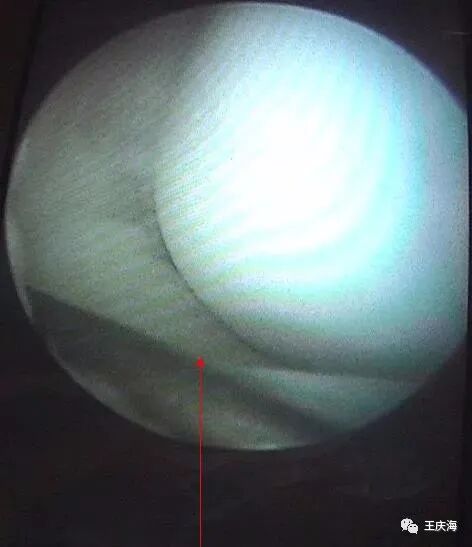

关节镜:作为盘状半月板诊断的金标准。

盘状半月板边缘已达髁间